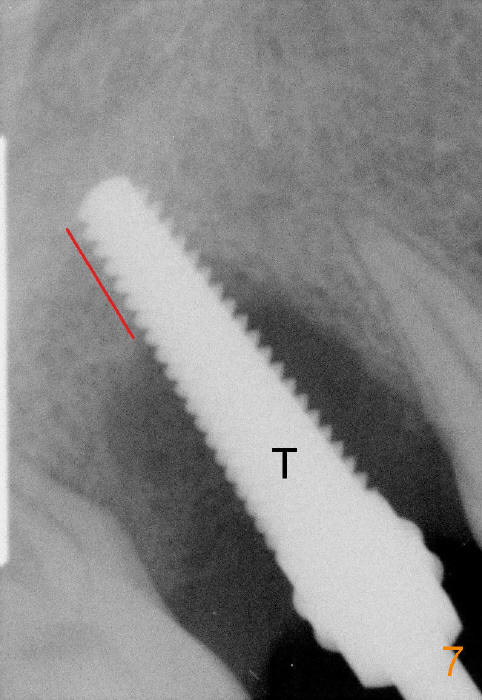

When a 4.5x20 mm tap (Fig.7 T) is inserted, the new bone gained is limited (red line).